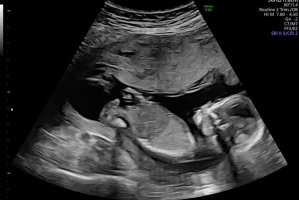

Noen som vil gjette her? 12+5. Usikker på om nub synes på disse bildene?

Jordmor tippet jente. Vi så nub mye tydeligere på skjerm. Ganske lang, rett og en liten vinkel oppover på tuppen. Da lå baby med god bøy på rygg. Andre steder så jeg den sto rett ut.

Senere sa jordmor det kunne se ut som gutt fra andre vinkler.